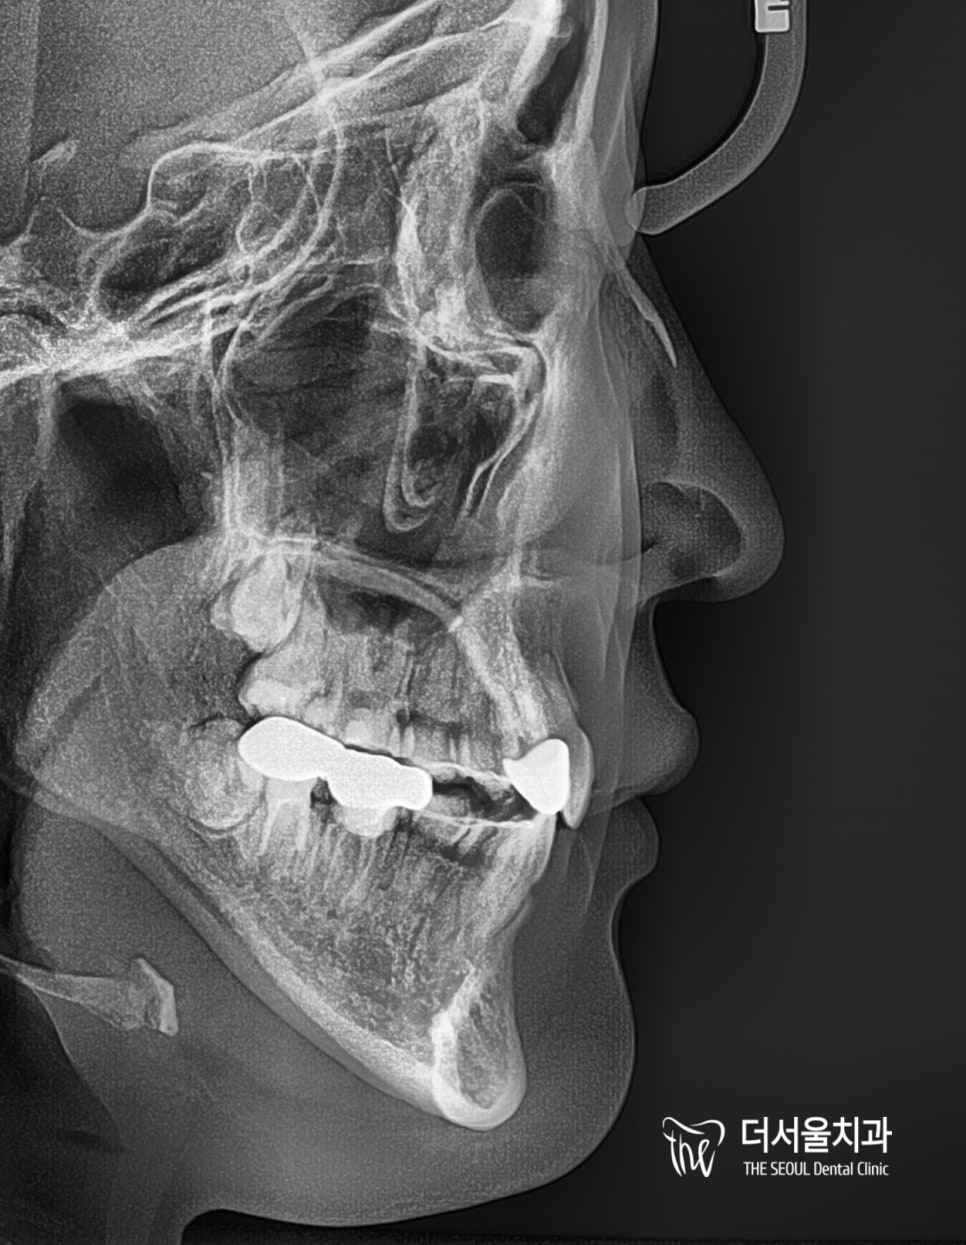

측면 ceph를 보면 돌출된 구강은 아니었기에

큰 변화는 찾아볼 수 없었는데요.

그래도 좀 더 자연스럽고 매끄러운 입매를 갖게 되었습니다.

자, 이것만 봐서는 어디가 나아졌는지

알아채기 어려우실 텐데요.